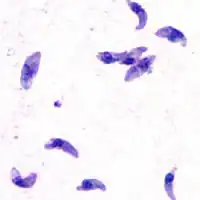

| Tacozoítos de T. gondii | |

O Toxoplasma gondii é um protozoário parasita intracelular obrigatório do grupo dos Apicomplexa, como outros parasitas como o Plasmodium. Há pouca variação entre os toxoplasmas presentes em diferentes partes do globo, podendo-se dizer que há, basicamente, três estirpes. A cepa 1 é altamente virulenta e responsável pelos casos de encefalite grave em imunodeprimidos e passagem transplacentária. As cepas 2 e 3 são avirulentas. As cepas 1, 2 e 3 são comuns na Europa e nos Estados Unidos. Mesmo a cepa 1, a mais agressiva das três, não causa tanto problemas oculares como as cepas atípicas, encontradas no sul do Brasil. Estas cepas atípicas são mais agressivas e causam lesões oculares em um grande número de pessoas. O surgimento destas cepas ocorreu possivelmente devido a essa região ter uma alta taxa de contaminação do meio ambiente, propiciando que ocorram recombinações genéticas do parasita[16][17][18]. O ciclo do toxoplasma é bastante flexível, posto que todas as suas formas são infectantes. Assim, ele pode reproduzir-se se as formas excretadas nas fezes dos gatos forem ingeridas por mamíferos ou outros felídeos por contaminação de água e alimentos, por exemplo, e também infectar o homem pelo mesmo modo, que, por sua vez, também pode infectar-se pela ingestão da carne de mamíferos contendo cistos com bradizoítas. Somente os gatos liberam estruturas infectantes nas fezes.

O T.gondii assume diferentes formas em diferentes estágios do seu ciclo.

O ciclo inicia-se pela ingestão de cistos presentes em carne (por exemplo, de porco, rato ou coelho), pelos felídeos. A parede do cisto é dissolvida por enzimas proteolíticas do estômago e intestino delgado, o parasito é liberado do cisto, penetra nos enterócitos (células da mucosa intestinal) do animal e replica-se assexuadamente dando origem a várias gerações de Toxoplasma (taquizoítos) através da reprodução assexuada. Após cinco dias dessa infecção, inicia-se o processo de reprodução sexuada, em que os merozoítos formados na reprodução assexuada dão origem aos gametas. Os gâmetas masculino (microgameta) e feminino (macrogameta), descendentes do mesmo parasita ou de dois diferentes, fundem-se dando origem ao ovo ou zigoto, que após segregar a parede cística dá origem ao oocisto. Este é expulso com as fezes dos animais após nove dias (cada gato expulsa mais de 500 milhões de oocistos em cada defecação).

Já no exterior, sofre divisão meiótica (esporulação) após 1 a 5 dias dependendo da temperatura e disponibilidade de oxigênio, formando-se dois esporocistos cada um com quatro esporozoítos. Uma forma altamente resistente a desinfectante pode durar cinco anos em condições úmidas. Estes são activados em taquizoítos se forem ingeridos por outro animal, chamado hospedeiro intermediário: por exemplo, um rato ou coelho que coma erva em que algum gato ou outro felídeo tenha defecado ou uma criança ou adulto que mexa com os dedos em material contaminado com fezes e depois leve-os à boca. Os taquizoítos podem se infectar e replicar em todas as células dos mamíferos, exceto nas hemácias. Uma vez ligados a uma célula do hospedeiro, o parasito penetra na célula e forma um vacúolo parasitóforo, dentro do qual se divide. A replicação do parasito continua até que seu número no interior da célula atinja uma massa crítica que provoca a ruptura da célula, liberando parasitos que irão infectar outras células adjacentes. A maior parte dos taquizoítos é eliminada pelas respostas imunes humoral e celular do hospedeiro. Algumas dessas formas produzem cistos, contendo muitos bradizoítos, ocorrendo em vários órgãos do hospedeiro, mas persistem no SNC e nos músculos. A formação de cistos é uma forma de evasão ao sistema imunológico do hospedeiro. Se o animal for caçado e devorado por um felídeo, os cistos libertam os parasitas dentro do seu intestino, infectando o novo hóspede definitivo.